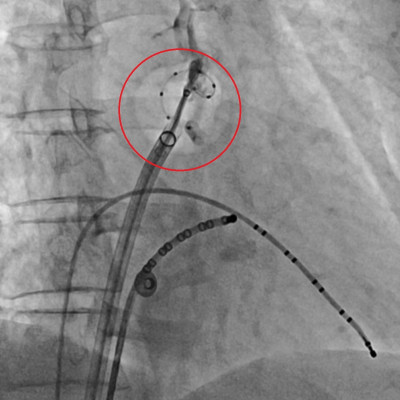

53歲陳先生2年多前感到心臟不適且心悸嚴重,就醫檢查發現他的左心室肌肉較肥厚且心律不整,診斷為心肌病變合併心房顫動,服用藥物舒緩症狀,但去年開始,病患心悸症狀日趨嚴重,就醫後,醫師為陳先生進行冷凍氣球肺靜脈隔離術,手術完成後2天就出院,恢復狀況良好,不再被心悸所困擾。

53歲陳先生兩年多前感到心臟不適且心悸嚴重,就醫檢查發現他的左心室肌肉較肥厚且心律不整,診斷為心肌病變合併心房顫動,服用藥物舒緩症狀,但從去年開始,病患心悸症狀日趨嚴重,生活品質大幅下降,經就醫討論,醫師為陳先生執行冷凍氣球肺靜脈隔離術,手術完成後兩天即出院,恢復狀況良好,不再被心悸所困擾。